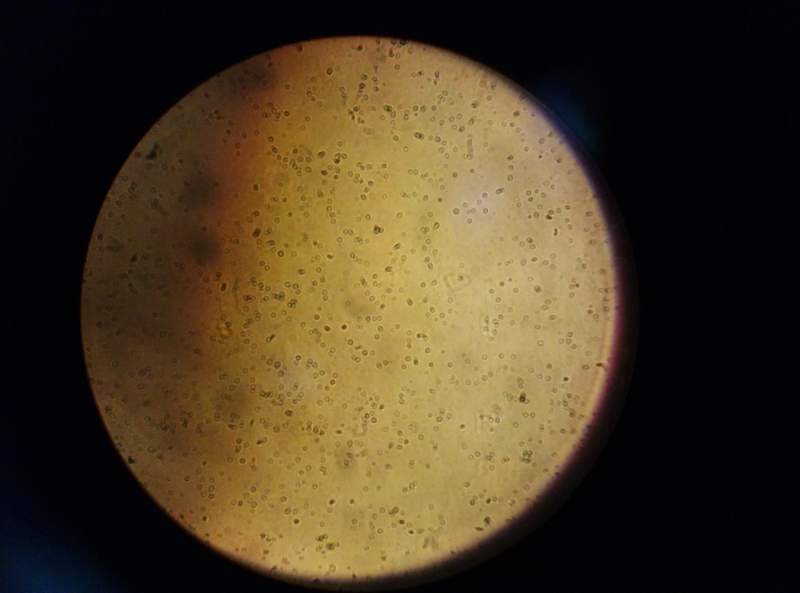

请各位高手帮我看看,我这是外周血提取的单个核细胞,最底层的是什么东西啊?谢谢

图片真心不清楚

首先得确认下你是用什么培养的,三层瓶还是别的什么

第二,是否是血小板或者别的细胞,比如单核细胞等等

我提取的是外周血单核细胞,体外进行培养,现在不了解现在培养瓶里的到底是不是单核细胞,请教您一下,希望得到你的帮助,谢谢,这是我最近拍的图片,

仅镜下来看,应该悬浮的居多,从形状和状态看,部分为单核细胞,也有部分淋巴细胞,当然还有别的细胞成分

再者,你这是外周血提取后培养多长时间的照片,第0天(提取当日算)还是第4天等等,有时添加完某些因子后,细胞会在发生贴壁后重新悬浮起来。

准确的鉴定单核细胞,可以做一下流式鉴定